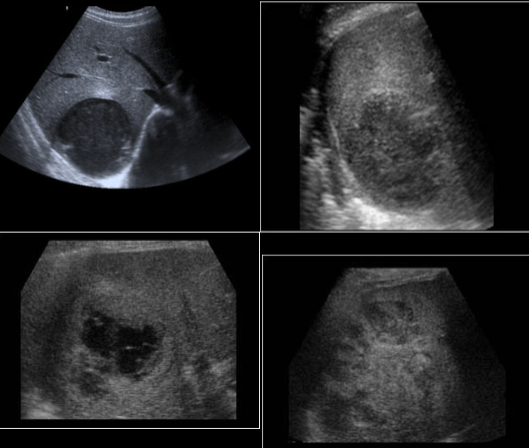

echinococcal cyst (squiggle lines is the water lily sign)

echinococcal cyst

hepatic candidiasis